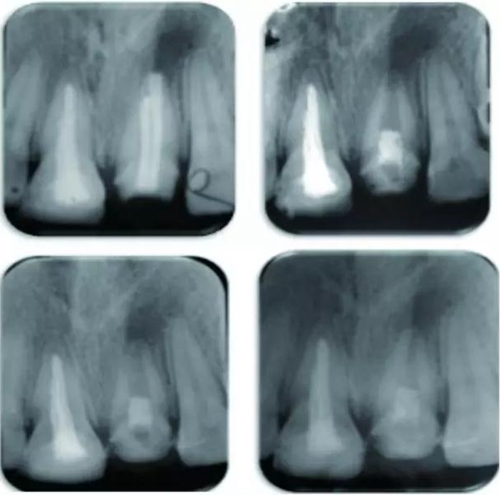

8月13日在線發(fā)表于《牙體牙髓病學雜志》(J Endod)的兩個成功病例顯示,對于根管治療后持續(xù)性根尖周炎患牙的再治療,牙髓再生治療術(shù)或有應用的潛能。

例為兩名年齡分別為26歲和12歲的男性患者,各有一顆恒牙(牙位分別為21與35)因患有根管治療后持續(xù)性根尖周炎而需進行再治療。用Carvene 牙膠溶解劑和ProTaper普通旋轉(zhuǎn)式再治療根管銼去除患牙根管內(nèi)充填的牙膠,接著進一步用旋轉(zhuǎn)再治療銼和大量次氯酸鈉對根管進行化學機械法清理,然后用Metapaste 干燥根管。對21和35兩患牙進行牙髓再生術(shù)治療。將根尖周的出血引入消毒后的根管內(nèi),用礦物三氧化物聚合物(MTA)填料覆蓋血塊,根管口修復材料填充。

結(jié)果為,兩患牙分別在隨訪13個月及14個月時表現(xiàn)出根尖周炎的臨床恢復體征和/或癥狀。21患牙顯示出根管變窄以及根尖部硬組織沉積而形成根尖封閉。

3.jpg

圖 21治療全過程,圖A 為治療前根尖片,圖B 為術(shù)后根尖片,圖C 顯示治療7 個月后根尖陰影縮小,圖D顯示治療后13個月根管口變窄